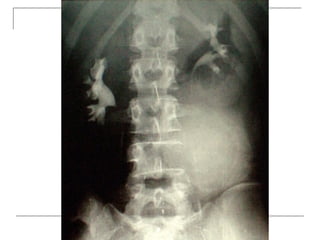

Plain radiograph

 AP

-loss of lumbar lordosis

-reduced disc space

-osteophytes

-deformity

-fracture (increase interpedicular distance)

-osteoporosis

-pedicle disruption

 Lateral

-fracture/wedging

-kyphosis

-spondylolisthesis

 Oblique

-spondylolysis (SCOTTIE DOG)

Plain x-rays